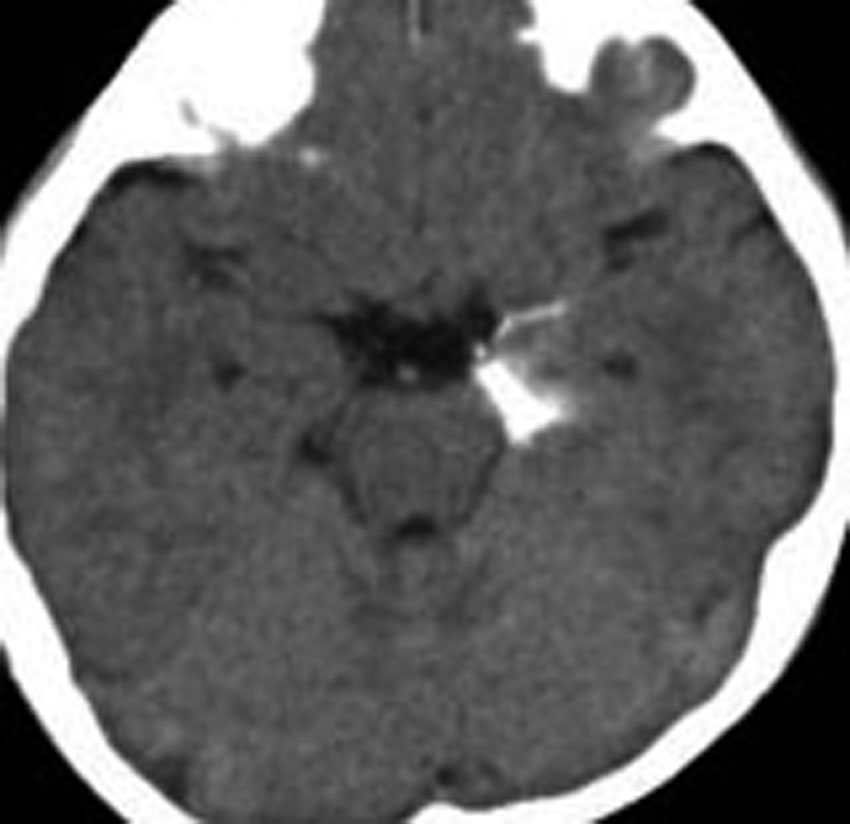

第4室床過誤腫の典型例です

新生児期より動作停止と右眼瞼のちく搦,4ヶ月で右眼の閉眼と口角の引きつれ(顔面けいれん)が目立つようになりました。2歳時には数十秒ごとに発作を繰り返していました。

MRIでは橋の背側(第4脳室床)にT1/T2で等信号の隆起(腫瘤)がみられました。

手術中の顔面筋電放電をモニターしたものです。過誤腫の摘出によって沈静化消失しています。

結果的に過誤腫をほぼ全摘出してしまったのですが,脳幹背側なので神経核損傷のリスクを伴います。亜全摘出でも発作は止まるとされています。手術中のモニターで放電が無くなればそこで過誤腫の摘出を中止して良いのでしょう。